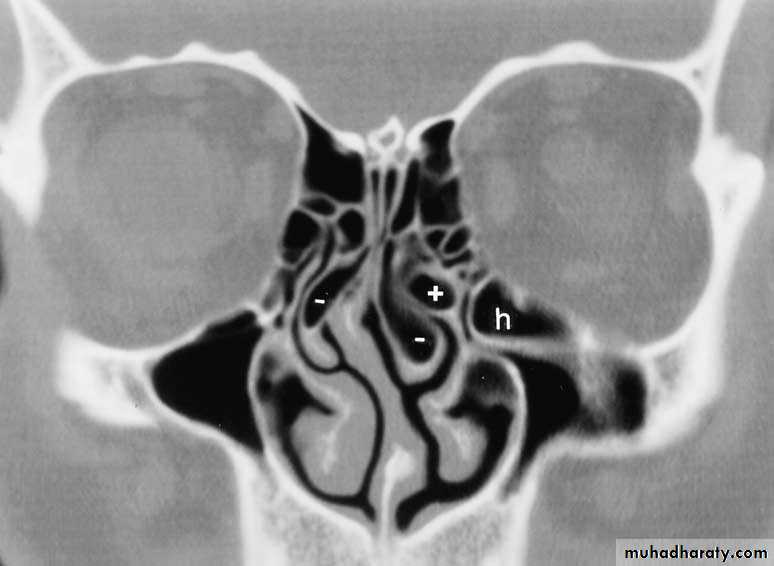

Lateral wall

Maxillary sinusEthmoid Sinus